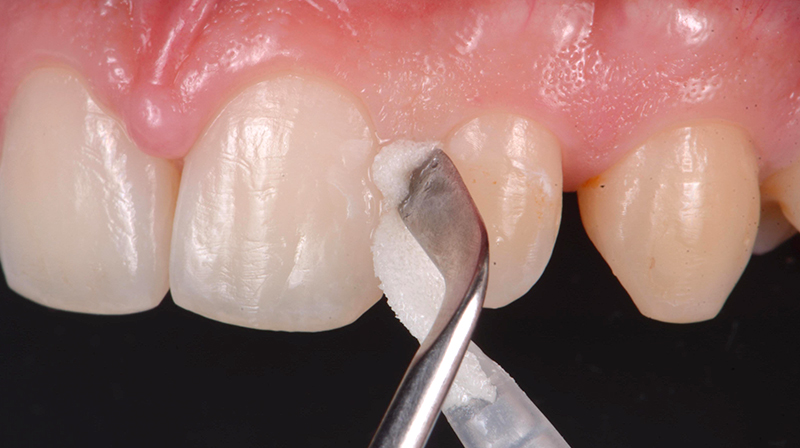

Prima dell’applicazione, è fondamentale detergere accuratamente la superficie dentale al fine di rimuovere la pellicola acquisita mediante ipoclorito di sodio al 2% per 20 secondi e quindi risciacquare e asciugare (Fig. 1). Successivamente è necessario rimuovere eventuali depositi inorganici, mordenzando con Acido Ortofosforico al 35-37% per 20 secondi. Una volta terminato, aspirare e risciacquare (Fig. 2).

Fig. 1 - Rimozione della pellicola organica acquisita con Ipoclorito di sodio al 2% (Da: G. Sammarco. Cariologia Clinica. Quintessence publishing Italia, 2025).

Per applicare il prodotto sulla lesione, isolare l’elemento da trattare con dei semplici rulli di cotone (non è richiesto l’utilizzo della diga di gomma) e distribuire il prodotto uniformemente sulla lesione, premendo bene la spugnetta in modo da far uscire il liquido, anche esercitando una pressione sull’applicatore mediante uno strumento quale una spatola di Heideman (Fig. 3). Grazie alla sua capacità di penetrare nelle microporosità e alla sua elevata affinità per l’idrossiapatite, il peptide riesce a raggiungere i siti danneggiati all'interno dello smalto demineralizzato fino alla profondità della lesione. Così, nel caso di lesioni cariose iniziali prossimali, è sufficiente premere la spugna dal lato buccale e linguale della zona prossimale. Poi, lasciare agire per circa 5 minuti la soluzione, al fine di permettere al peptide di auto-assemblarsi e formare la matrice peptidica che guiderà la remineralizzazione. Al termine del periodo di posa, il paziente può essere dimesso con la raccomandazione di non bere e non mangiare per circa 30 minuti.

Fig. 3 - Applicazione di CURODONT™ REPAIR (Da: G. Sammarco. Cariologia Clinica. Quintessence publishing Italia, 2025).